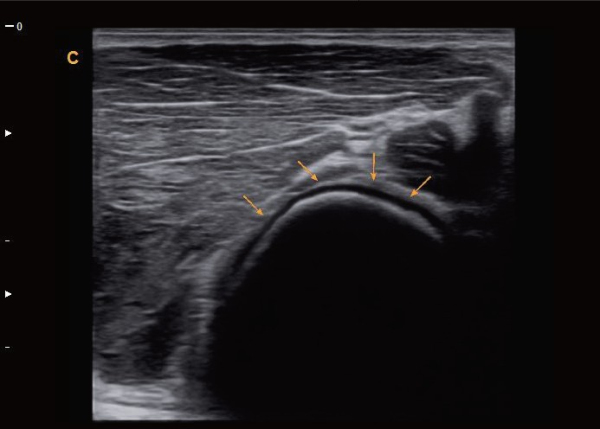

With Super Needle, clinicians can see needle inside tissue more clearly during medical procedures.Needle angle up to ±30°